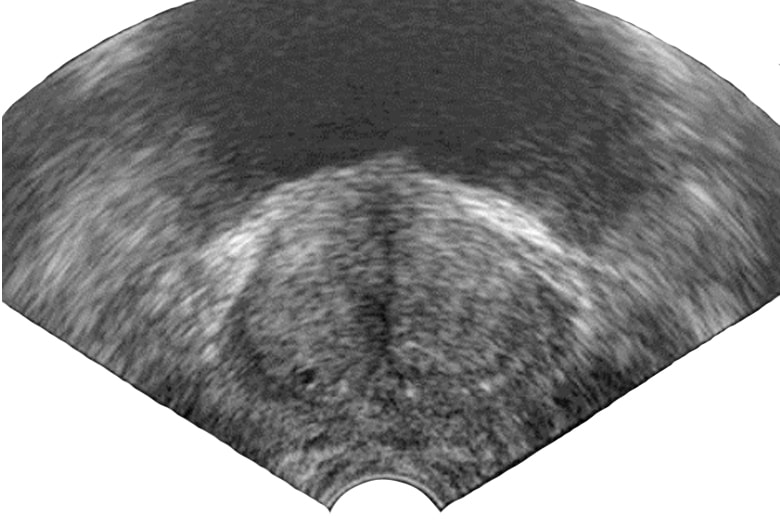

При ДГПЖ на ультразвуковых сканограммах определяется увеличение предстательной железы разной степени, которая в виде округлого образования с ровными контурами вдается в просвет мочевого пузыря (рис. 3). У некоторых больных предстательная железа приобретает грушевидную форму за счет изолированного увеличения средней доли. Более точно оценить состояние и направление роста предстательной железы при ее доброкачественной гиперплазии можно после трансректального УЗИ.

Рис. 3. Трансректальная ультрасонограмма больного с доброкачественной гиперплазией предстательной железы